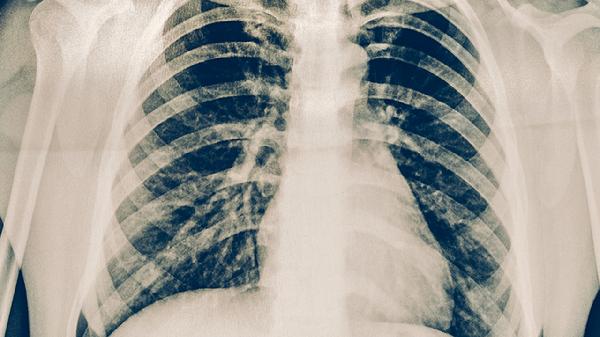

肺结核患者除规范用药外,需保证每日优质蛋白摄入如鸡蛋、瘦肉,补充维生素A/D增强黏膜修复。注意居室通风消毒,咳嗽时掩住口鼻。避免劳累、戒烟酒,定期复查胸部影像学及痰菌检测。出现药物不良反应或症状加重时需立即就医调整方案。